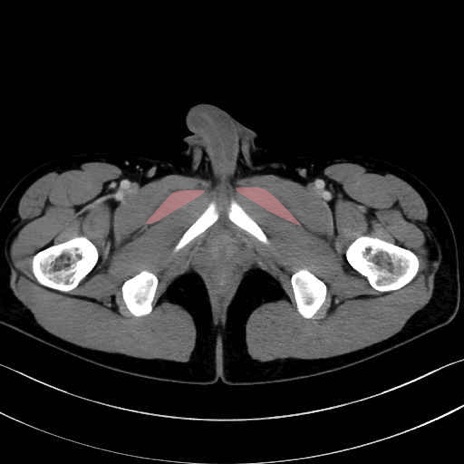

短内転筋(Adductor brevis) のCT画像の解剖

短内転筋 (Adductor brevis)